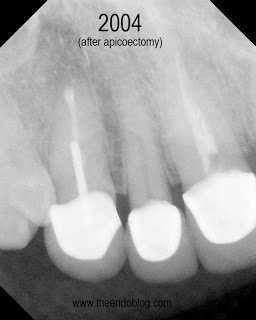

9.5 year recall. Tooth is fully functional, asymptomatic with radiographic healing. Apicoectomy has preserved the tooth and the periodontium for an extended period of time.